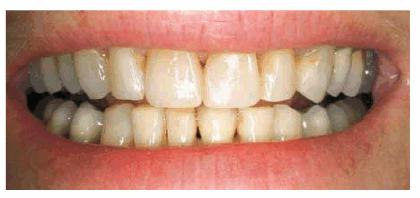

Figures 29-12A to C show a 75-year-old woman who presented

with severe root caries and moderate periodontal disease. Her daughter, who

disclosed that her mother was difficult to please, referred her. The daughter

was very supportive of her mother receiving dental treatment; however, her

mother was initially not interested. The mother did not think that the esthetic

aspect of dentistry was important. During consultation with the dentist, the

mother was informed of the infection in her mouth and the potential effect that

this could have on her future health and functionality. The patient consented

to have the maxillary arch restored with fixed prosthodontics. She refused to

accept treatment for her mandibular teeth, preferring to use her existing

partial denture. Figures 29-12D, and 29-12E show the final result after periodontal and

prosthodontic treatment. Although the patient was not particularly grateful to

have the dental treatment, her family was thrilled to have the caries infection

removed and the esthetic appearance improved. The patient lived with her

esthetically improved appearance for an additional 13 years.

Figure 29-12A to C: This 75-year-old woman had severe root caries and moderate periodontal disease.

Figure 29-12D: Although this woman stated that she would "just as soon have her teeth extracted," she was motivated to have both periodontal and prosthodontic treatment.

Figure 29-12E: The patient's smile after esthetic dental treatment shows just how much she appreciated her dental treatment.